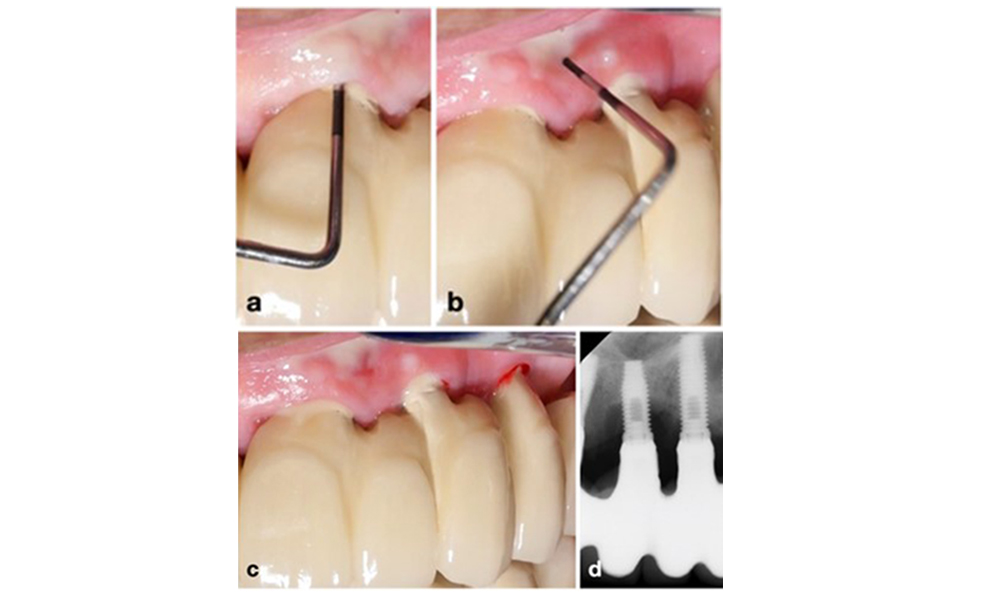

La péri-implantite est identifiée par (1) des signes d'inflammation similaires à la mucosite, (2) des preuves radiographiques de perte osseuse après la cicatrisation initiale et (3) une augmentation de la profondeur de sondage par rapport aux mesures prises peu après la mise en place de la reconstruction prothétique (figure 2). En l'absence de radiographies antérieures, un niveau osseux radiographique de ≥ 3 mm, accompagné d'un saignement au sondage et d'une profondeur de sondage ≥ 6 mm, indique une péri-implantite.

Restauration de l'arcade complète avec péri-implantite à des degrés divers sur certains implants. L'implant en position 21 est sévèrement atteint avec des profondeurs de sondage allant jusqu'à 9 mm (a), un saignement au sondage, une suppuration du sillon péri-implantaire et une fistule vestibulaire (b-c) ; la radiographie montre une perte osseuse d'environ 50 % pour l'implant atteint de péri-implantite en position 21, tandis que l'implant en position 23 présente une perte osseuse limitée, correspondant approximativement à ce que l'on peut attendre après la cicatrisation initiale pour ce type d'implants (d).

Figure 2. Restauration de l'arcade complète avec péri-implantite à des degrés divers sur certains implants. L'implant en position 21 est sévèrement atteint avec des profondeurs de sondage allant jusqu'à 9 mm (a), un saignement au sondage, une suppuration du sillon péri-implantaire et une fistule vestibulaire (b-c) ; la radiographie montre une perte osseuse d'environ 50 % pour l'implant atteint de péri-implantite en position 21, tandis que l'implant en position 23 présente une perte osseuse limitée, correspondant approximativement à ce que l'on peut attendre après la cicatrisation initiale pour ce type d'implants (d).

La perte osseuse attendue après la cicatrisation initiale, attribuée au remodelage de l'os marginal, varie en fonction de facteurs tels que le système ou le type d'implant. Par exemple, une perte osseuse de 1 à 2 mm est généralement considérée comme "normale" pour les implants au niveau de l'os avec une connexion externe (figure 2d, implant en position 23).